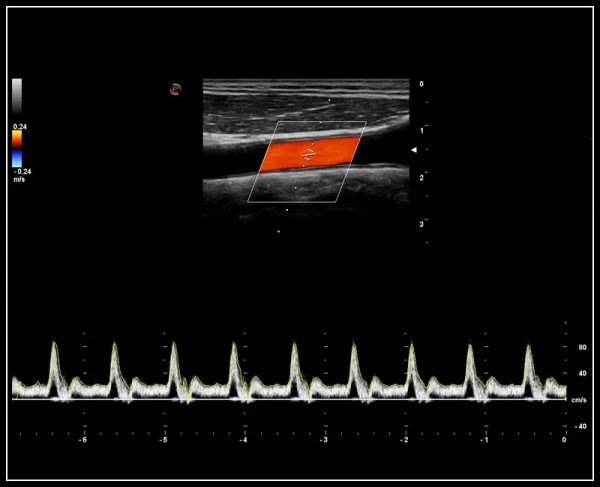

ULTRA-Color Doppler rangli xaritalash usullari: yuqori sezuvchanlik, chuqur kirish va yuqori aniqlik

EasyTrace algoritmi. Doppler rejimlarida vizualizatsiyani avtomatik sozlash algoritmi, aks ettirish burchagini to'g'rilaydi va bir necha soniya ichida miqdoriy ma'lumotlarni taqdim etadi.